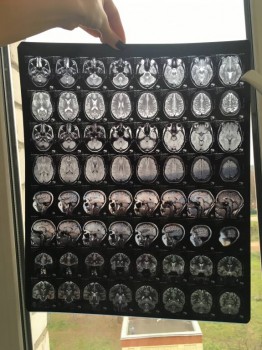

Общалась с Вами по телефону неделю назад, после того как мне на МРТ продиагностиргвали кисту шишковидной железы головного мозга.

Отправляю Вам снимки МРТ, Очень надеюсь на вообще мнения о причине возникновения кисты.

Снимок головы

Здравствуйте, Евгения. Пленки мрт желательно смотреть (зная и видя пациента) на специальном экране, в полном размере. Отсюда можно увидеть, что они есть. Не более. Вполне логично, если врачи сделают заключение по месту проведения исследования. Если останутся сомнения, проконсультируйтесь в другой клинике, только отвезите сами снимки.